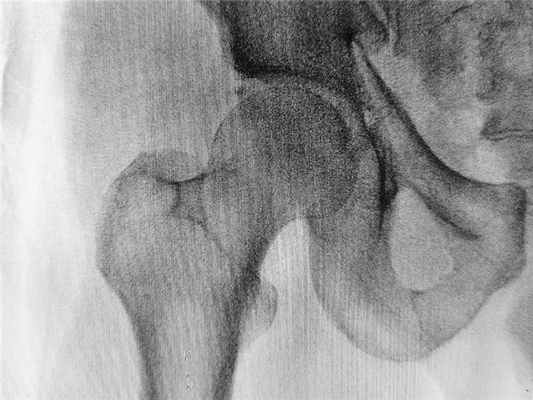

Тазовые кости участвуют в образовании трех сочленений: лобкового симфиза, парного крестцово-подвздошного сустава и парного тазобедренного сустава. Форму тазобедренного сустава можно представить в виде шара, расположенного в глубоком гнезде округлой формы. Лобковый симфиз и крестцово-подвздошный сустав малоподвижны, а в шаровидном (или, точнее, чашеобразном) тазобедренном суставе, обеспечивающем одновременно устойчивость тела и подвижность ноги, возможен большой объем движений.

Внутри вертлужной впадины находится головка бедренной кости, которая связана с телом бедренной кости при помощи шейки. Часто шейку бедренной кости называют "шейкой бедра", но это жаргонизм. Несколько ниже шейки бедра находятся костные возвышения, называемые большим и малым вертелами. К ним прикрепляются мощные мышцы.

Тазобедренный сустав прикрыт мышцами ягодичной области сзади и мышцами передней группы бедра спереди. Головка бедренной кости, расположенная в ацетабулярной впадине, покрыта суставным хрящом. Суставной хрящ в тазобедренном суставе в среднем достигает 4 мм в толщину, имеет очень гладкую поверхность белесоватого цвета и плотноэластическую консистенцию. Благодаря наличию суставного хряща значительно уменьшается трение между соприкасающимися суставными поверхностями.

Суставная капсула укреплена тремя связками, соединяющими кости таза и шейку бедренной кости. Прочная подвздошно-бедренная связка (связка Бигелоу) имеет форму перевернутой буквы V и состоит из двух отдельных пучков, отходящих от нижнего края передней нижней подвздошной ости и прикрепляющихся к медиальному и латеральному отделам передней межвертельной линии. Лобково-бедренная связка по спирали проходит между лобковой поверхностью запирательного отверстия и медиальным отделом шейки бедренной кости. Седалищно-бедренная связка окружает верхнюю поверхность шейки бедренной кости и прикрепляется к переднему ее отделу. Рисунок, вид сзади: седалищно-бедренная связка (связка Бертена) начинается широким основанием от седалищной кости и по спирали проходит к переднему краю большого вертела. Рисунок, коронарный срез через тазобедренный сустав: визуализируется утолщение центральной части суставной капсулы, получившее название круговой зоны. Круглая связка отходит от ямки головки бедренной кости к поперечной связке. Вертлужная впадина с трех сторон окаймлена суставной губой, а снизу-поперечной связкой. Суставной хрящ вертлужной впадины благодаря своей форме получил название полулунного. Вертлужная ямка расположена в центре медиальной стенки вертлужной впадины и суставным хрящом не покрыта. Суставная губа в центре прикрепляется к полулунному хрящу. Артрография, передне-задняя проекция: между вертлужной впадиной и межвертельной линией визуализируется контур сустава. Суставная сумка на уровне круговой зоны сужается, образуя завороты на границе головки и шейки бедренной кости, а также у основания последней. Контрастный препарат поступает в верхний отдел вертлужной ямки, очерчивая контур суставной губы. Артрография, боковая проекция с отведением бедра: определяются передний и задний суставные завороты. Дефект заполнения в области вертлужной ямки обусловлен жировой подушкой. Тонкая линия контрастного препарата отделяет суставные хрящи вертлужной впадины и головки бедренной кости. Сверху отмечается нормальное заполнение перилабрального заворота.